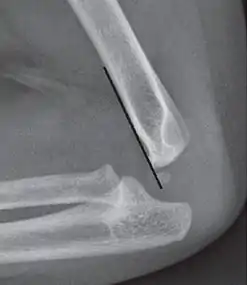

On lateral view of the elbow, there are five radiological features should be looked for: tear drop sign, anterior humeral line, coronoid line, fish-tail sign, and fat pad sign/sail sign (anterior and posterior).[3][8]

Anterior humeral line - It is a line drawn down along the front of the humerus on the lateral view and it should pass through the middle third of the capitulum of the humerus.[9] If it passes through the anterior third of the capitulum, it indicates the posterior displacement of distal fragment.[8]

Fat pad sign/sail sign - A non-displaced fracture can be difficult to identify and a fracture line may not be visible on the X-rays. However, the presence of a joint effusion is helpful in identifying a non-displaced fracture. Bleeding from the fracture expands the joint capsule and is visualized on the lateral view as a darker area anteriorly and posteriorly, and is known as the sail sign.[8]

Coronoid line - A line drawn along the anterior border of the coronoid process of the ulna should touch the anterior part of the lateral condyle of the humerus. If lateral condyle appears posterior to this line, it indicates the posterior displacement of lateral condyle.[8]

Anterior and posterior sail sign in a child who has a subtle supracondylar fracture

Anterior humeral line (black line), with normal area passed on the capitulum of the humerus colored in green in a 4 year old child.[9]